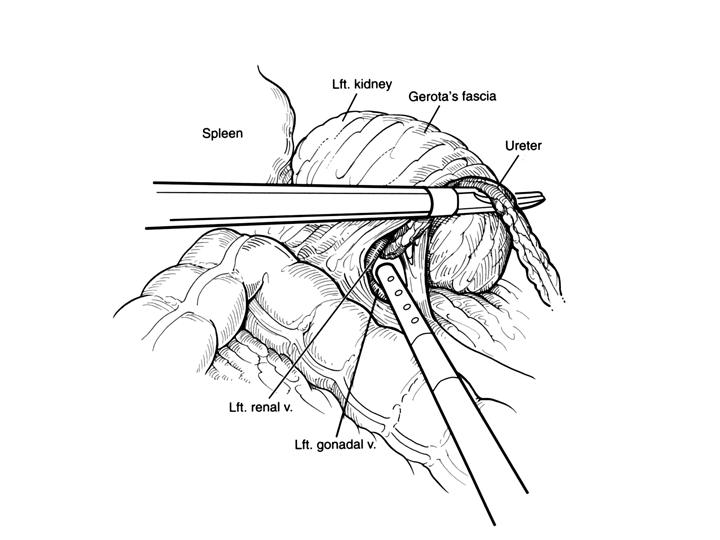

Surgical illustrations visually depict operative techniques, surgical anatomy, and complex procedures. They are created with high anatomical accuracy and serve as a visual bridge between complex surgical knowledge and learners, clinicians, or patients.